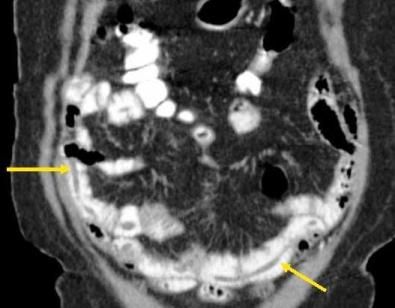

Treatment was initiated with ciprofloxacin and flagyl for a presumed infectious colitis. Because of the cecal findings, the patient was admitted for possible appendicitis. Results of a subsequent CT scan showed large worms in the distal jejunum and ileum (Figures 1-4). Stool samples were sent for an ova and parasite (O&P) test. The patient improved and was discharged home.

Figures 3 and 4